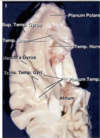

Key gyri on the lateral surface of the frontal lobe

Superior frontal gyrus

Middle frontal gyrus

Inferior frontal gyrus (pars triangularis, pars orbitalis, pars opercularis)

Precentral gyrus